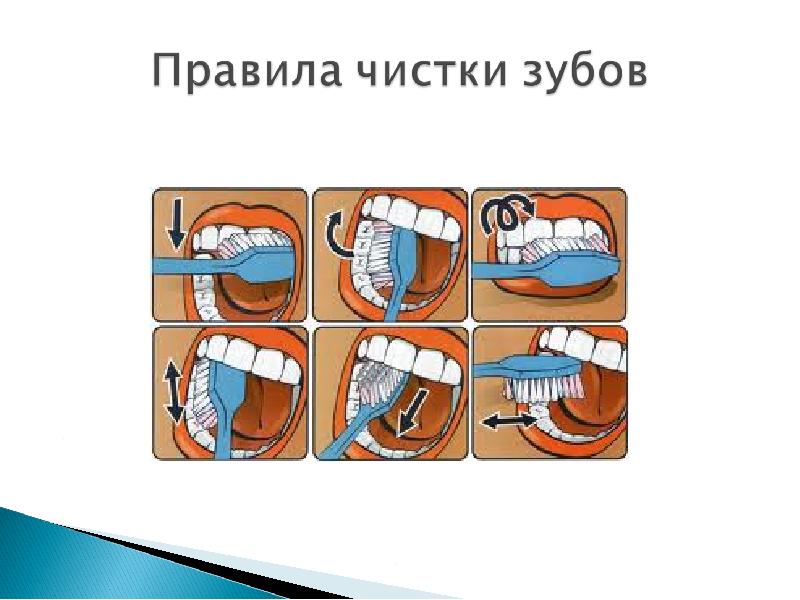

Этапы чистки зубов: Правильный уход за полостью рта

Раздел: Снимки-подсказки